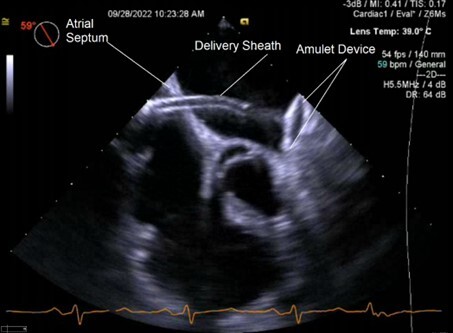

Amplatzer Amulet

The Amulet is the next generation of the Amplatzer cardiac plug and is a self-expanding device for LAA occlusion implanted from the femoral vein using a transseptal approach. (See Figures 3 and 4.) It consists of a distal lobe, which conforms to the inner LAA wall, connected by an articulated waist to a proximal disk, which seals the LAA ostium. In an initial evaluation, 24 out of 25 patients underwent successful device implantation without any procedural stroke, pericardial effusion, or device embolization. At follow-up, there was no residual leak > 3 mm or device embolization, demonstrating the safety and feasibility of the device.45

Figure 3. 2D TEE Image of Amulet Device Deployment into Left Atrial Appendage |

![]() |

TEE: transesophageal echocardiography |